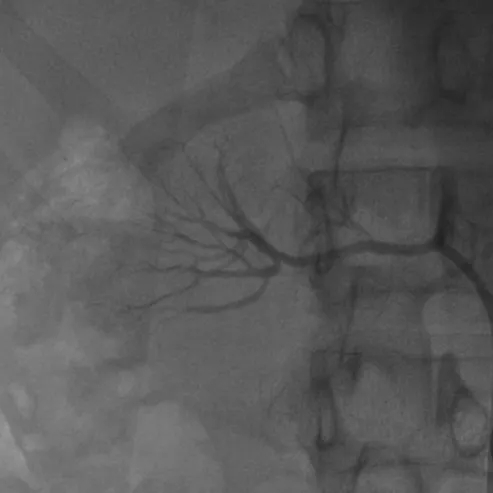

经过周密评估,团队制定了精细的介入手术方案,并特邀北京专家指导,由济南市中心医院高血压科介入团队关玉庆、孔庆赞、刘淼主任共同施术。术中造影证实了术前判断:右肾动脉中远段血栓形成、血管近乎闭塞。在精准操作下,导丝顺利通过闭塞段,经球囊扩张后,血流恢复通畅。

术后右肾动脉血流恢复

术后效果立竿见影:患者血压迅速恢复正常,复查肾功能、尿微量白蛋白等关键指标均显著改善。一度被判定“近乎无功能”的肾脏,重新焕发了生机。“真的感觉自己重生了!”女孩在康复后激动地表示。